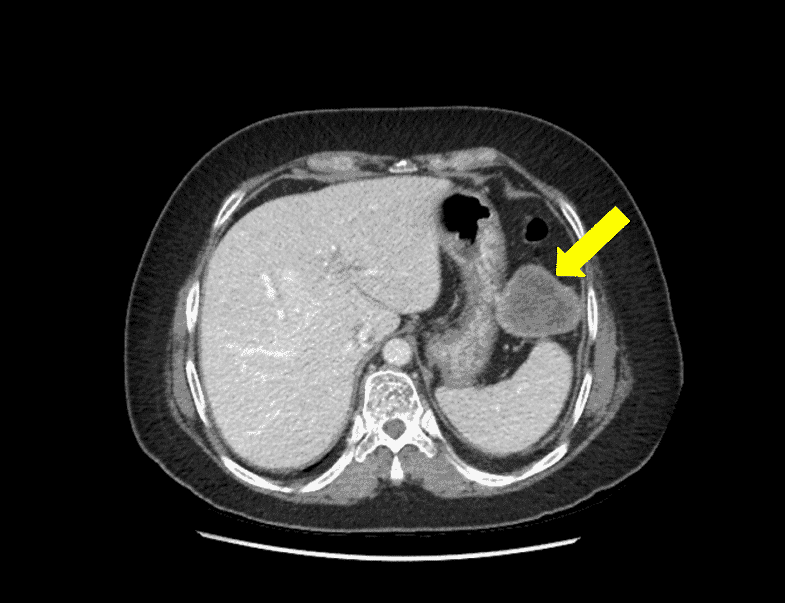

A proper workup of GIST requires imaging. GIST is best evaluated by cross-sectional imaging such as computed tomography (CT). They appear on CT scans as solid masses with smooth contours that are easily identified by IV contrast (Figure 1). Larger masses can show evidence of hemorrhage, necrosis, and degenerative areas on CT imaging, creating cavities or cysts that may contain air, air and fluid, or contrast medium. CT imaging can also assess for adjacent organ invasion and metastases [11].

Figure 1. Computed Tomography Scan of the Abdomen and Pelvis with IV Contrast.